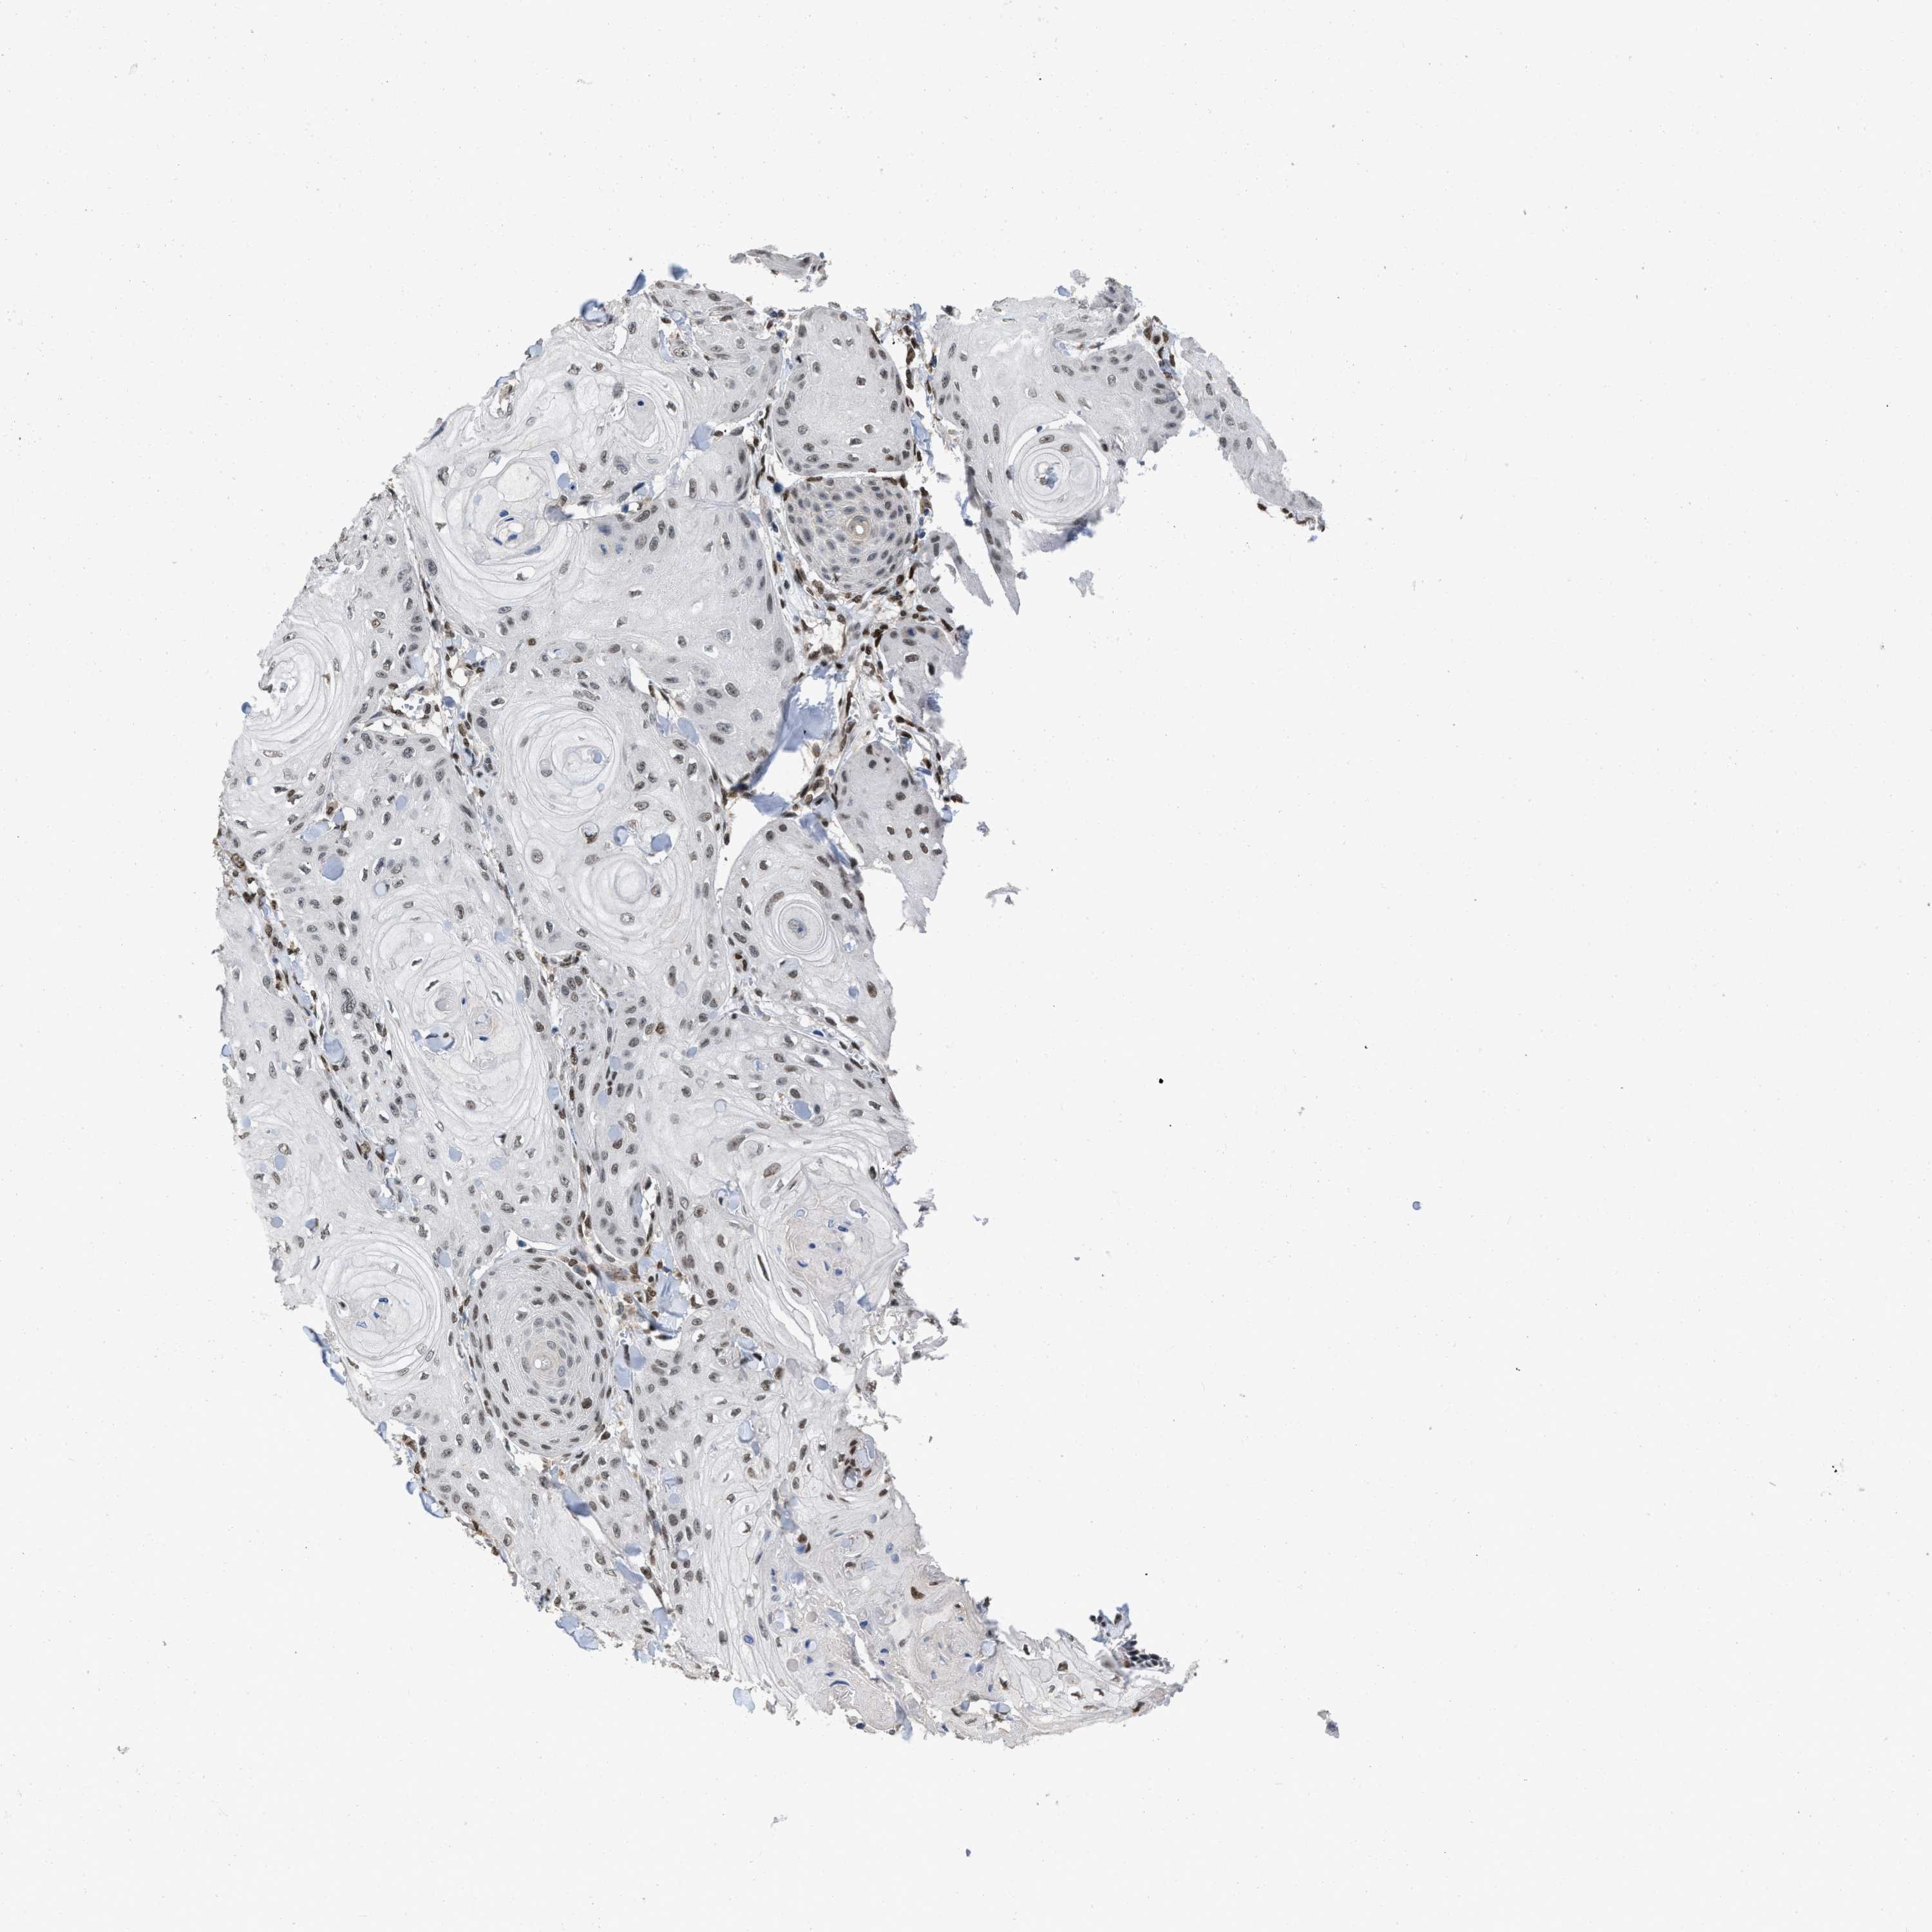

SKIN CANCER - Protein expressioni

A mouse-over function shows sample information and annotation data. Click on an image to view it in a full screen mode. Samples can be filtered based on level of antibody staining by selecting one or several of the following categories: high, medium, low and not detected. The assay and annotation is described here.

Each image is clickable and will lead to virtual microscopy that enables deeper exploration of all samples and also displays staining intensity scores, fraction scores and subcellular localization as well as patient and tissue information for each sample.

Antibody HPA019123

Staining

High

Medium

Low

Not detected

Intensity

Strong

Moderate

Weak

Negative

Quantity

>75%

75%-25%

<25%

None

Location

Nuclear

Cytoplasmic/membranous

Cytoplasmic/membranous,nuclear

Squamous cell carcinoma in situ, NOS